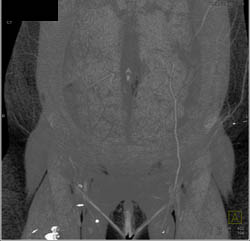

GSW Without Vascular Injury